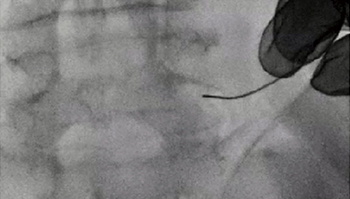

図8は、右腎瘻のカテーテル交換症例である。全体像(図8 a)から患者を移動することなく、右腎の一部を拡大し、カテーテル交換を行った(図8 b)。i-fluoro使用下での造影剤内のワイヤーやカテーテルの視認性も十分であった。図9は膀胱瘻造影症例で、i-fluoroを用いて骨盤部の拡大を行ったが、本症例も同様に必要な情報がきれいに視認できた。当院では、骨盤内の子宮卵管造影も行っているが、一度患者が天板に乗ると患者の移動が困難な検査の一つとして、i-fluoroの有用性を産婦人科とともに評価している。

図8 i-fluoroの使用例:右腎瘻カテーテル交換症例